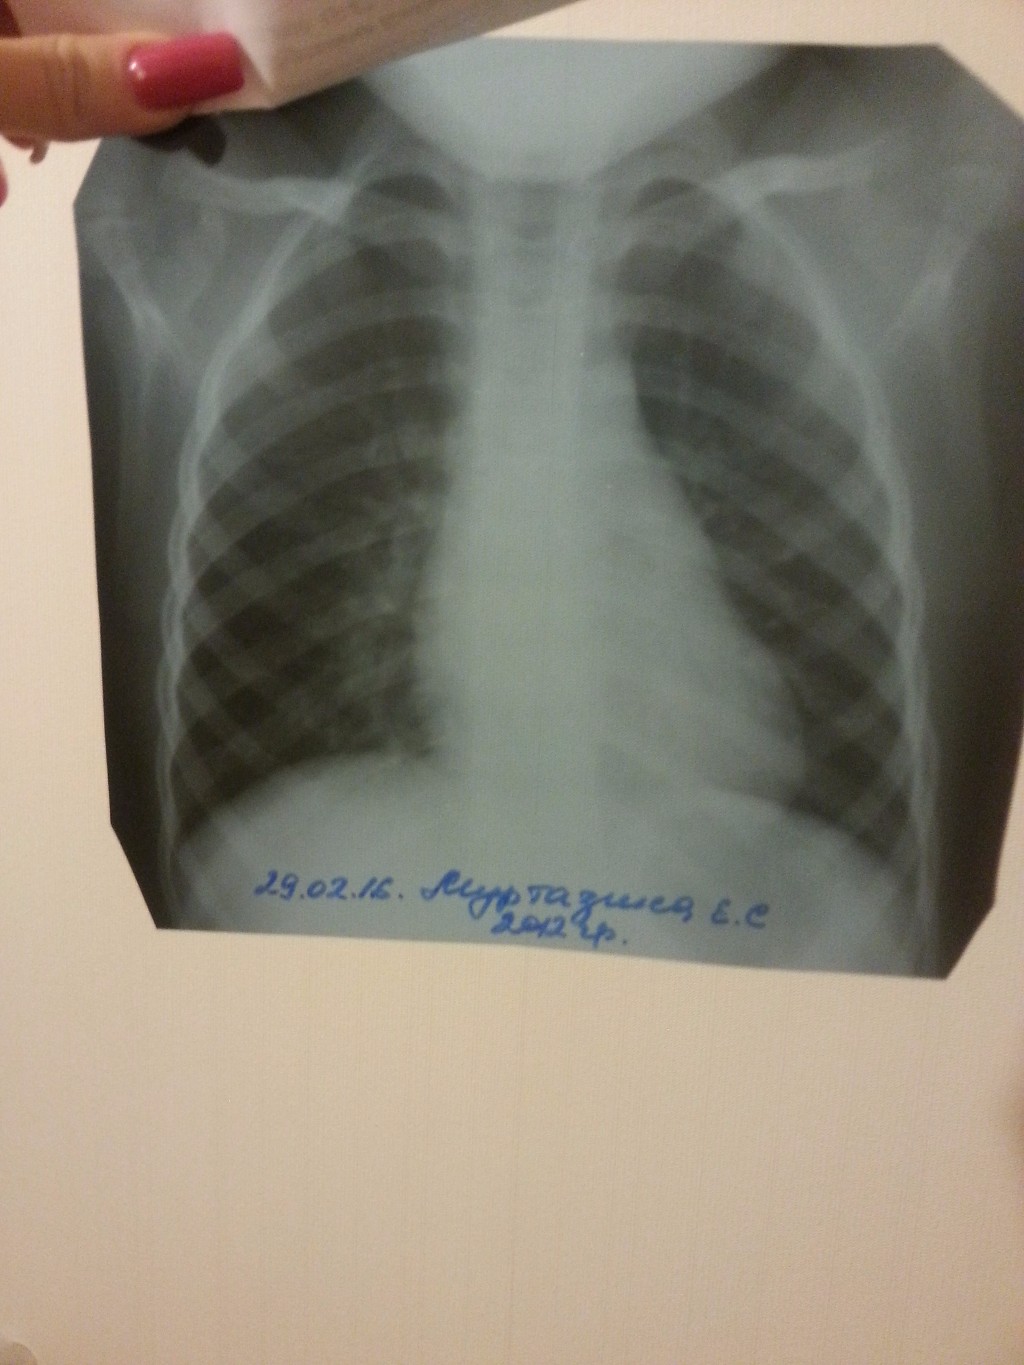

Организация рабочего пространства: стенды для рентгеновских снимков